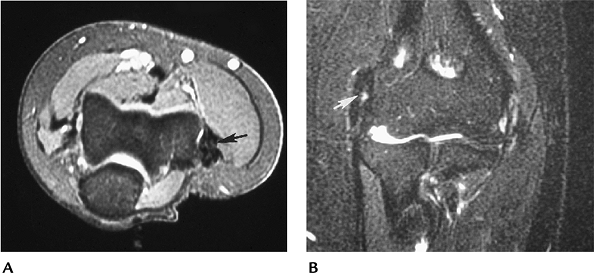

![]() |

FIGURE 8-22 Extensor tendinopathy. Axial (A) and coronal (B) T2-weighted images showing tendon thickening and abnormal signal intensity (arrow) in the extensor tendon.

FIGURE 8-23 Partial tear of the common extensor origin. Axial (A) and coronal (B) T2-weighted images showing increased signal intensity (arrow) resulting from a partial tear.